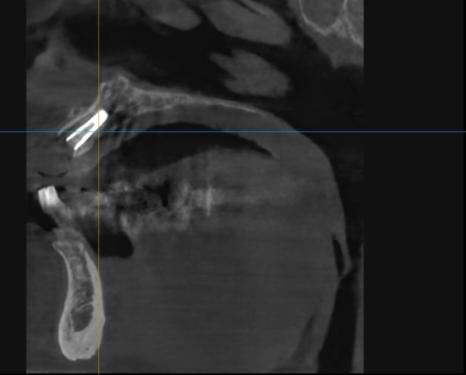

방사선 사진과 CT를 확인해보니

오래된 보철물 안쪽으로

2차 충치가 심하게 진행되어 있었고,

240315

특히 왼쪽 송곳니(#23)는 이미 치아 머리 부분이

부러져 뿌리와 분리된 상태였습니다.

뿌리 끝까지 염증이 퍼져

잇몸뼈가 많이 녹아있었기에,

안타깝게도 발치를 진행하기로 했습니다.

먼저 기존에 사용하시던

오래된 브릿지를 제거한 뒤,

염증이 심해 더 이상 살리기 어려운

치아 4개(#13, 21, 22, 23)를 발치했습니다.